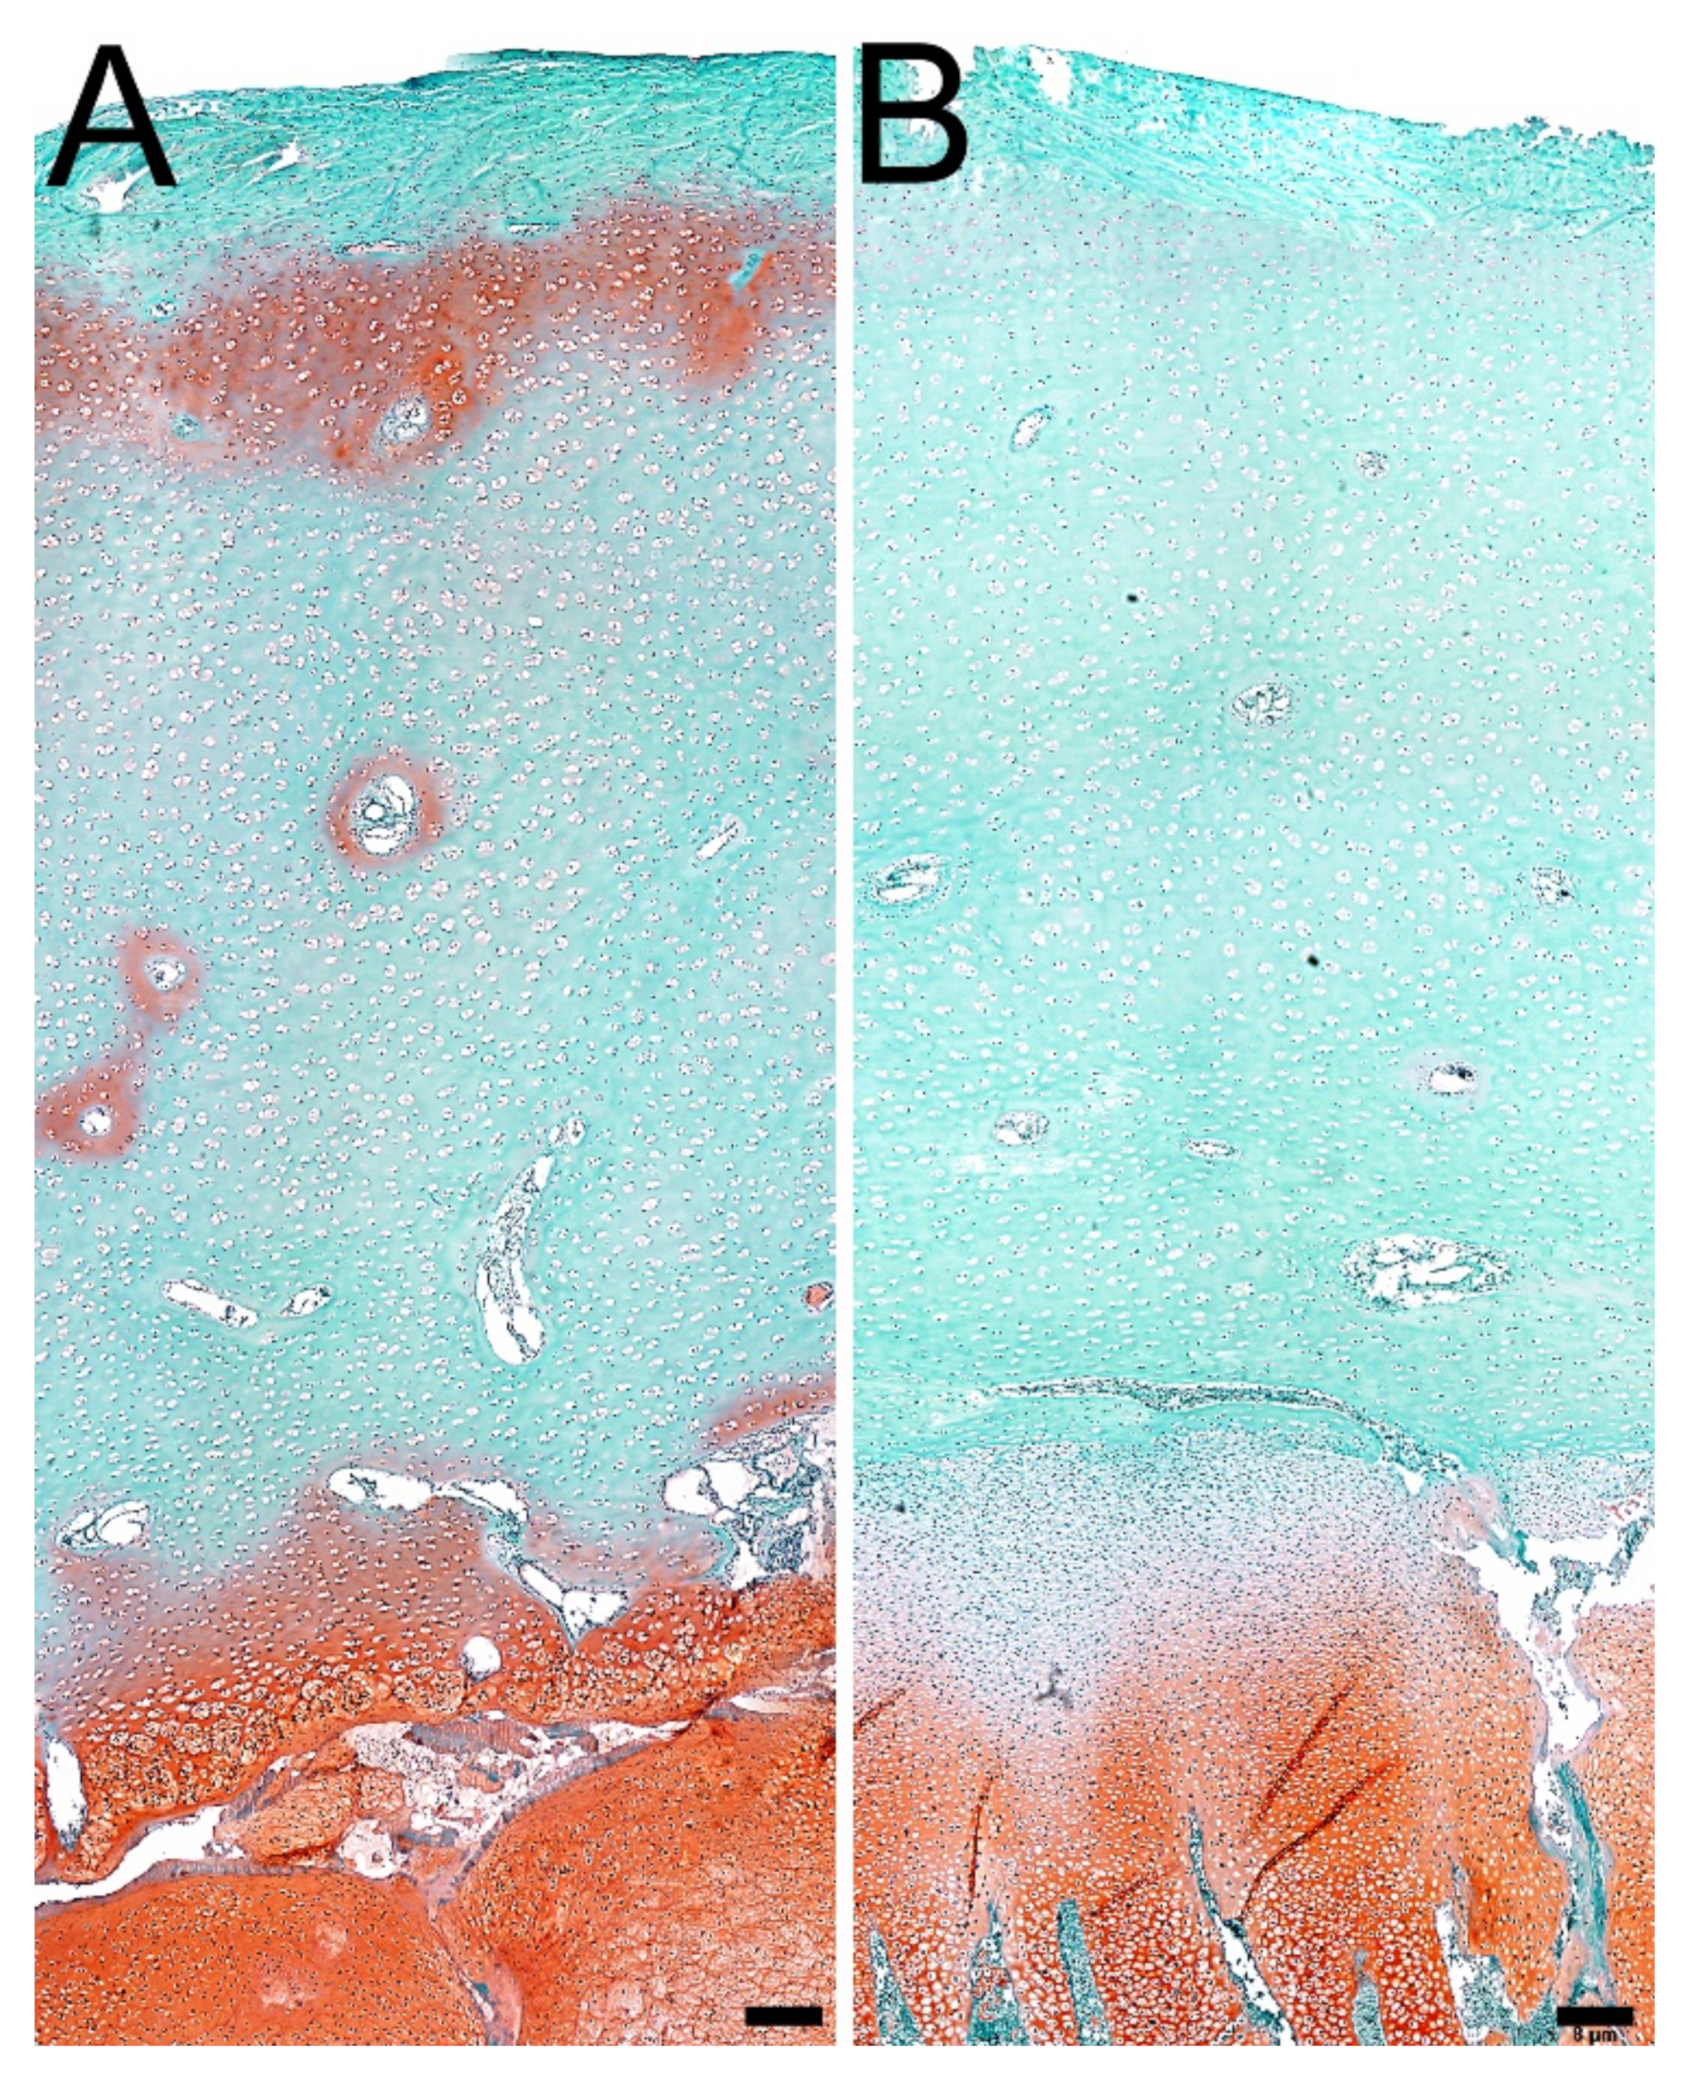

3.5. Proteoglycans in Articular Cartilage and Growth Plate Cartilage

3.6. Ash Content and Composition of the Mineral Fraction in Bone